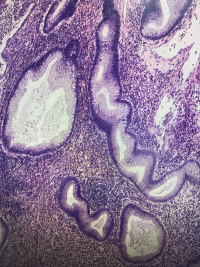

直肠息肉

一般病史

血便4天

灰红结节一枚,大小1✖️0.6✖️0.6cm,切面灰红,质软

管状腺瘤,低级别还是高级别?

幼年性息肉,灶性低级别

幼年性息肉?

幼年性息肉